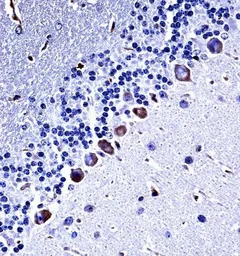

IHC-P analysis of mouse cerebellum tissue using GTX53489 Casein Kinase I gamma 3 antibody.

Dilution : 1:25